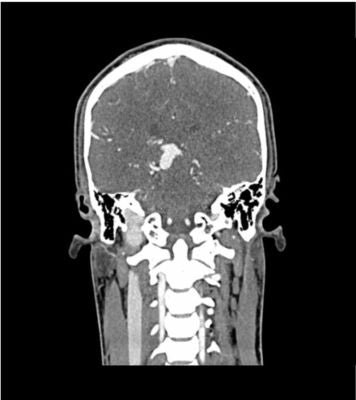

Description

This phantom simulates a contrast medium-enhanced head in the arterial phase (CT angiography). It covers the vertex to the fifth cervical vertebra. The right hemisphere has an arteriovenous malformation.

The phantom can be used in CT (including CBCT) to evaluate and optimize imaging performance and AI-enabled diagnosis. It is also suited for training purposes.